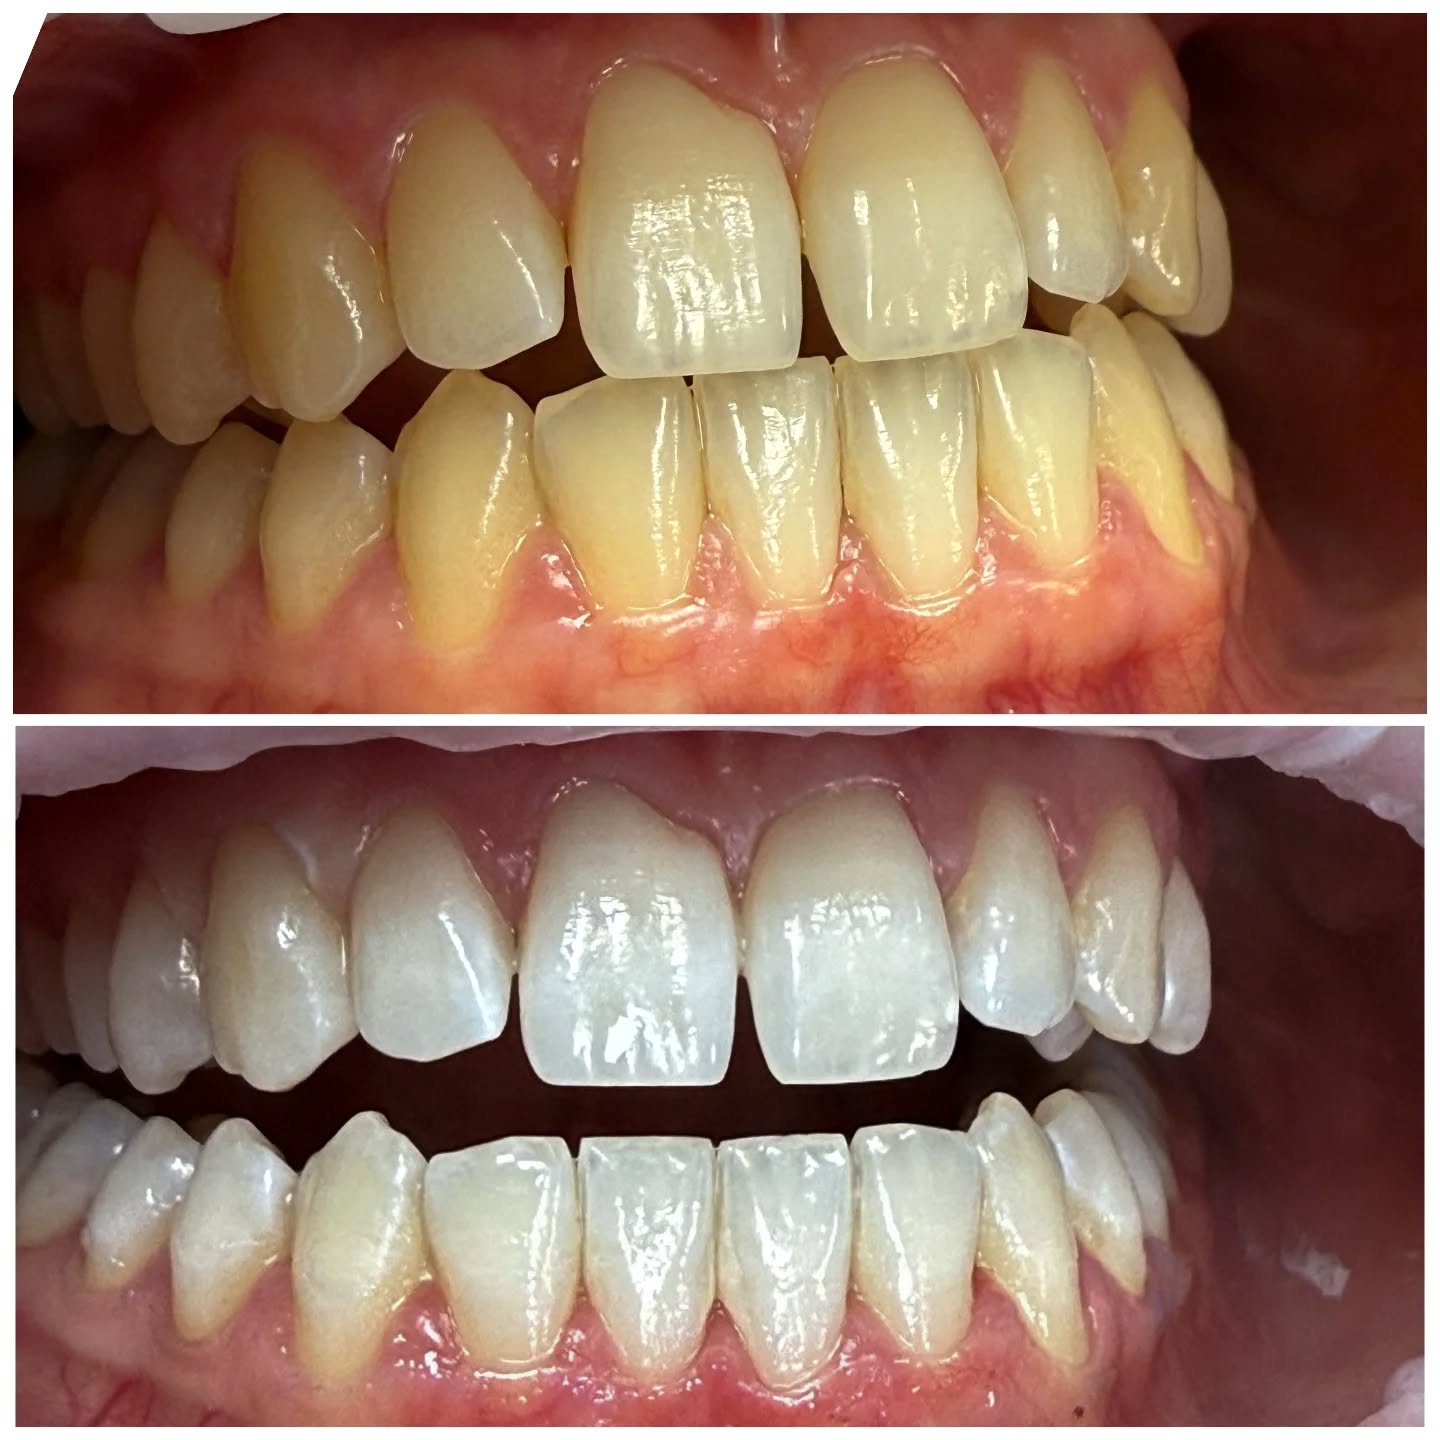

• Laserowe wybielanie zębów – nowoczesna i bezpieczna droga do śnieżnobiałego uśmiechu! 👄

Marzysz o białym uśmiechu, ale boisz się bólu i nadwrażliwości po zabiegu? Mamy idealne rozwiązanie – laserowe wybielanie zębów! 🦷

Dlaczego laser jest lepszy od tradycyjnej lampy?

➡️ Działa precyzyjnie i równomiernie

➡️ Skraca czas zabiegu

➡️ Mniejsze ryzyko podrażnień i nadwrażliwości

➡️ Efekty są widoczne szybciej i utrzymują się dłużej

📆 Zabieg składa się z dwóch wizyt – to gwarancja pełnego bezpieczeństwa i kontrolowanego efektu wybielenia.

🪥 Po wybielaniu kluczowa jest idealna higiena jamy ustnej – regularne szczotkowanie, nitkowanie i unikanie barwiących produktów pomogą utrzymać śnieżnobiały efekt na długo!

😬 A co jeśli masz zęby trudne do wybielenia?

Wtedy warto wspomóc się specjalnymi nakładkami do stosowania w domu, które podtrzymają efekt i pozwolą osiągnąć wymarzony kolor.